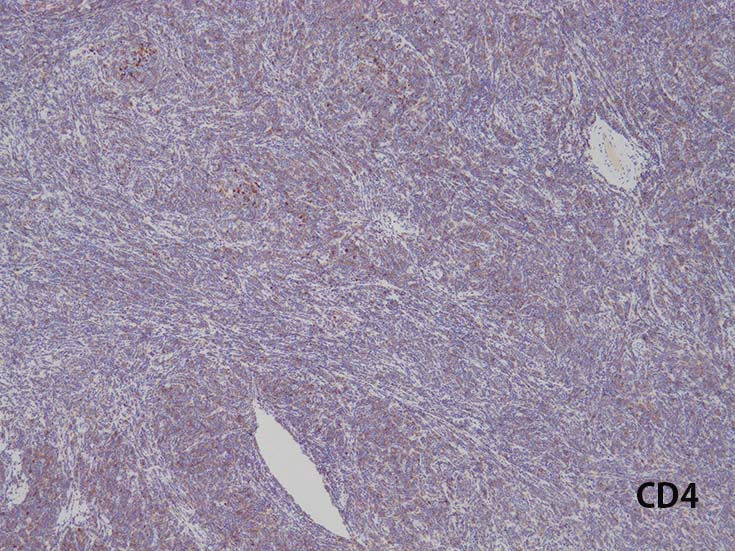

CD30

granzyme B

CD56

c-KIT(CD117)

Immunophenotype of T-ALL/ LBL

- TdT, CD34に加えて, CD99と CD1a陽性はT-lymphoblastsの前駆細胞の性質を確認するのに役立つ.

- CD1a, CD2, surface CD3 (dim), CD4, CD5, CD8は種々の程度に発現する.

- T-ALL はしばしば, CD4とCD8の double positive となる. またCD10が陽性になる

- CD4,CD8 double positiveはT-prolymphocytic leukaemiaでも認められる. CD10もPTCL(第一にはAITL)に陽性となることに注意.

- cytoplasmic CD3 のみがT-cell lineage特異的なマーカである.

- MPO, lysozymeは発現しない. CD13+, CD33+, CD13,CD33 both+ (19-32%). myeloid marker発現はT-ALL/LBLの診断を否定できない.

また,myeloid mraker発現があるからといって, T/myeloid mixed phenotype acute leukaemiaと診断してもいけない.

- まれにc-KIT(CD117)+; FLT3の活性化変異に関連する.